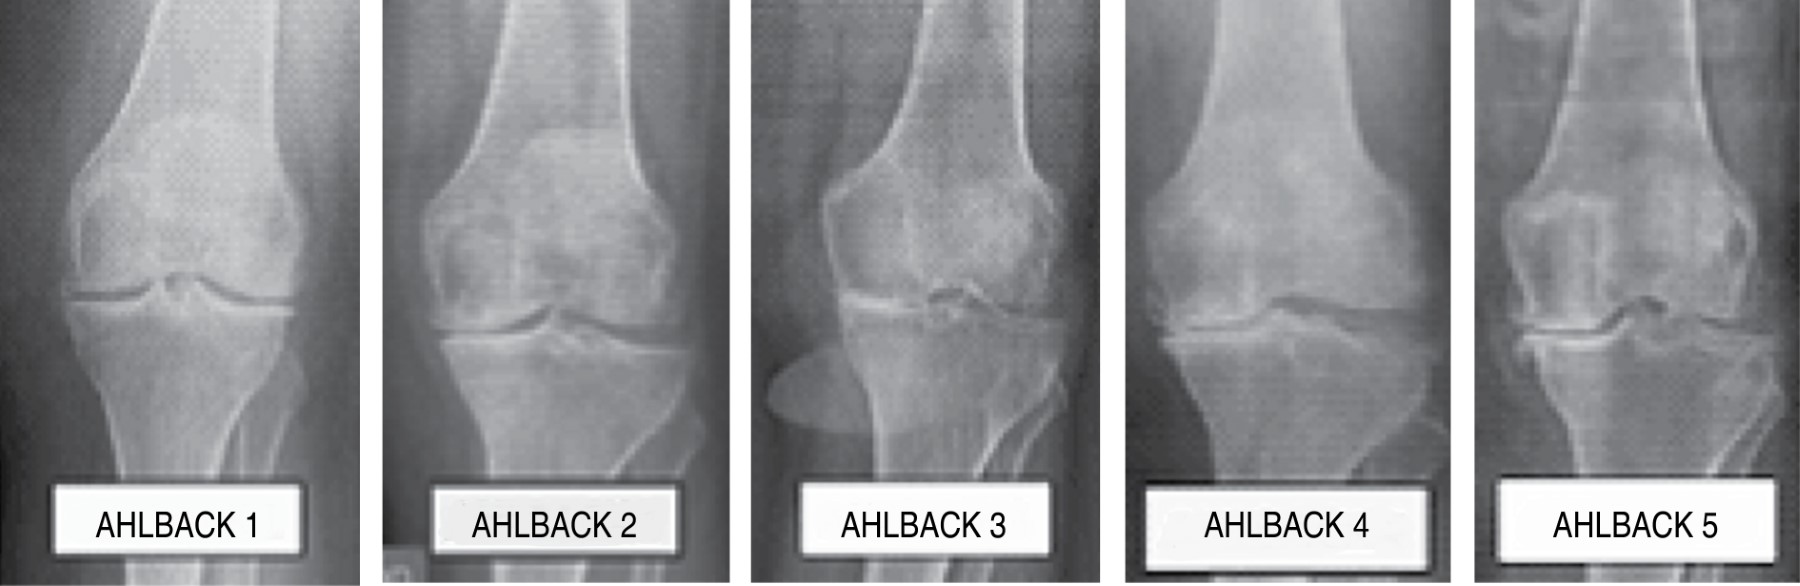

La osteoartrosis es el trastorno musculoesquelético más común encontrado en atención primaria.1 Como una enfermedad crónica está caracterizada por dolor y discapacidad física, siendo la rodilla la articulación más afectada.2 Según la OMS, afecta a 9.6% de los hombres y 18% de las mujeres > 60 años.3 En EUA, la tasa de incidencia anual estandarizada para la gonartrosis por edad y sexo por 100,000 habitantes fue de 240.4 En la mayoría de los casos, vamos a encontrar que no existe ningún factor determinante que origine la aparición de artrosis sin existir ninguna alteración articular preexistente, dentro de las causas secundarias destacan las postquirúrgicas, postinfecciosas y postraumáticas, donde desempeñan un papel fundamental las deformidades angulares residuales como el varo y valgo, que provocan distribución anormal de las cargas de peso.5 La presencia de factores de riesgo contribuye al aumento de la incidencia de la enfermedad en la población general, y se correlaciona con el grado de dolor articular experimentado por el paciente.6 Se ha encontrado relación de la obesidad y el tejido adiposo, ya que aumenta la síntesis de citocinas proinflamatorias, como el factor de necrosis tumoral alfa y las interleucinas (IL) 1, 6, 8 y 18, disminuyendo además las citocinas reguladoras como la IL-10.7 Se considera el dolor como síntoma primario y la principal causa de discapacidad funcional.8 Para la gradación radiológica de la gonartrosis se ha desarrollado la escala de Ahlbäck (Tablas 1 y 2) y la de Kellgren y Lawrence (Figura 1).9-11 La artroplastia total de rodilla (Figura 2) es considerada como el principal tratamiento y constituye al día de hoy el que consigue mejores resultados funcionales y de satisfacción a corto y mediano plazo.12 El uso de isquemia con mango neumático o elástico sigue muy arraigado en la práctica de la cirugía ortopédica, si bien es cierto que conlleva ventajas técnico-quirúrgicas, como una mejora en la visión quirúrgica al mantener un campo operatorio más limpio y reduce el tiempo operatorio, no es un procedimiento inocuo,13 ya que se le ha asociado con complicaciones trombóticas, vasculares, nerviosas, dolor intenso en el muslo, retardo en la cicatrización de la herida, cambios hemodinámicos inherentes al proceso de isquemia y reperfusión y disminución de rangos de movilidad.14,15

Figura 1